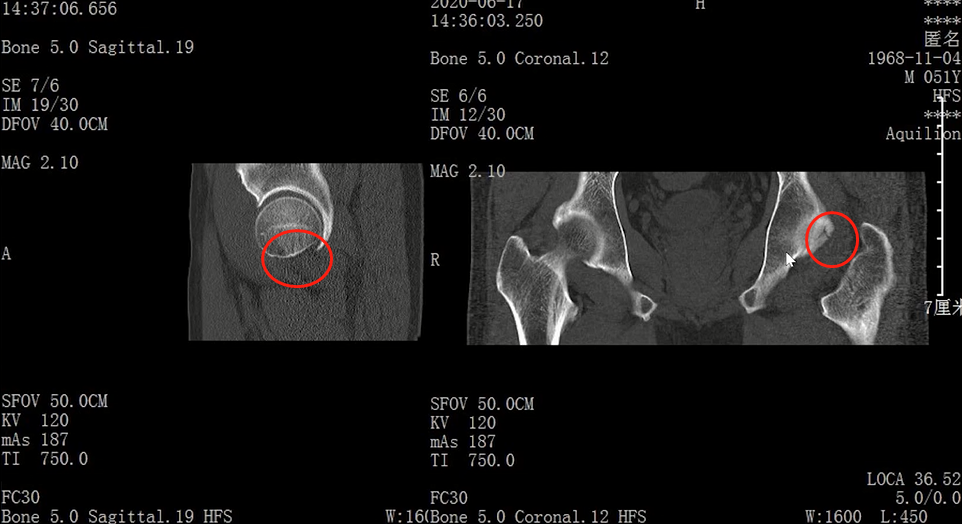

Lisfranc损伤在多发伤病人中常常容易漏诊,大约为 20-30%的漏诊率!